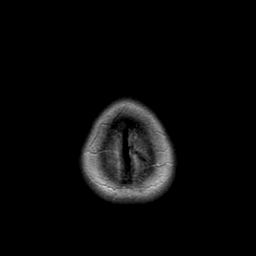

Metastatic bronchogenic carcinoma: proton density-weighted MR -- Slice #22

[Home][Help][Clinical] Slice 22